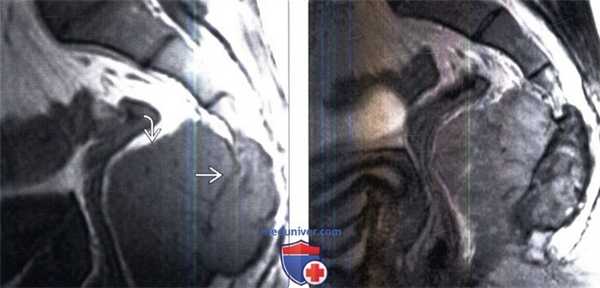

(Слева) Рентгенография в боковой проекции: визуализируются немного вспученный полностью литический очаг надколенника. Патологический очаг вполне типичен для хондробластомы, однако пациент старше большинства людей с этим заболеванием, поэтому также следует рассматривать вероятность гигантоклеточной опухоли.

(Справа) МРТ, сагиттальная проекция, режим Т2 с подавлением сигнала от жира: у этого же пациента визуализируется зона неоднородного сигнала низкой интенсивности Я, окруженная высокоинтенсивным патологическим очагом. Наличие такого низкоинтенсивного участка в структуре очага типично для гигантоклеточной опухоли и помогает подтвердить диагноз. (Слева) Рентгенография в ПЗ проекции: патологический очаг, занимающий большую часть половины таза. Очаг характеризуется значительной экспансивностью, однако имеет узкую переходную зону. Признаки мягкотканного компонента отсутствуют Здесь была подтверждена гигантоклеточная опухоль, которая может характеризоваться вспученностью и пузырчатостью.

(Справа) Рентгенография в ПЗ проекции: умеренно агрессивный очаг, распространяющийся от субартикулярной поверхности пястной кости в дистальном направлении с прорывом кортикального слоя и периостальной реакцией. Здесь следует рассматривать вероятность ГКО и энхондромы. (Слева) МРТ, аксиальная проекция, режим Т1: у этого же пациента визуализируется низкоинтенсивный патологический очаг с прорывом кортикального слоя и циркулярное мягкотканное образование.

(Справа) МРТ, сагиттальная проекция, режим Т2 с подавлением сигнала от жира: у этого же пациента визуализируется умеренно агрессивный очаг, характеризующийся смешанной: высокой и низкой интенсивностью сигнала. Такая неоднородность с выраженными низкоинтенсивными зонами типична для ГКО, которая и была подтверждена результатами биопсии. При энхондроме должна была определяться характерная хрящевая высокоинтенсивная дольчатость.